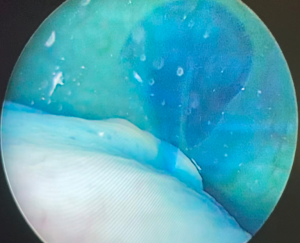

Once the fixation of the mesh to vagina is completed, the tail of the mesh is brought to the sacral promontory through the groove. Tensioning of the mesh is critical; the decision of how much pull the vaginal cuff depends on the maximal vaginal length. The procedure might be insufficient if the mesh is loose, and the patient may experience pain and discomfort if the mesh placed too tight. In our practice, this part is done manually while the surgical assistant inserts the EEA sizer into the vagina to measure the maximal vaginal length and pull back 1/3. While holding the mesh against the sacral promontory, 2 or 3 Gore-Tex® (Gore Medical, Newark, USA) or Ethibond® (Ethicon, Somerville, NJ, USA), 0 sutures are used to fixate the tail of the mesh to the anterior longitudinal ligament (Figure 6). We prefer to place these sutures vertically to avoid injuring any vessels, however they can be placed horizontally as well. Regardless, we would recommend placing these sutures broad and shallow under the ligament to provide enough strength without damaging the disk that may lay underneath the ligament. After the mesh is fully secured, redundant mesh at the promontory is removed. The mesh is then retroperitonealized using an absorbable suture (Figure 7). Intraoperative cystoscopy with indigotindisulfonate sodium (Indigo carmine™) is performed to evaluate the bladder and ureteral orifices (Figure 8).